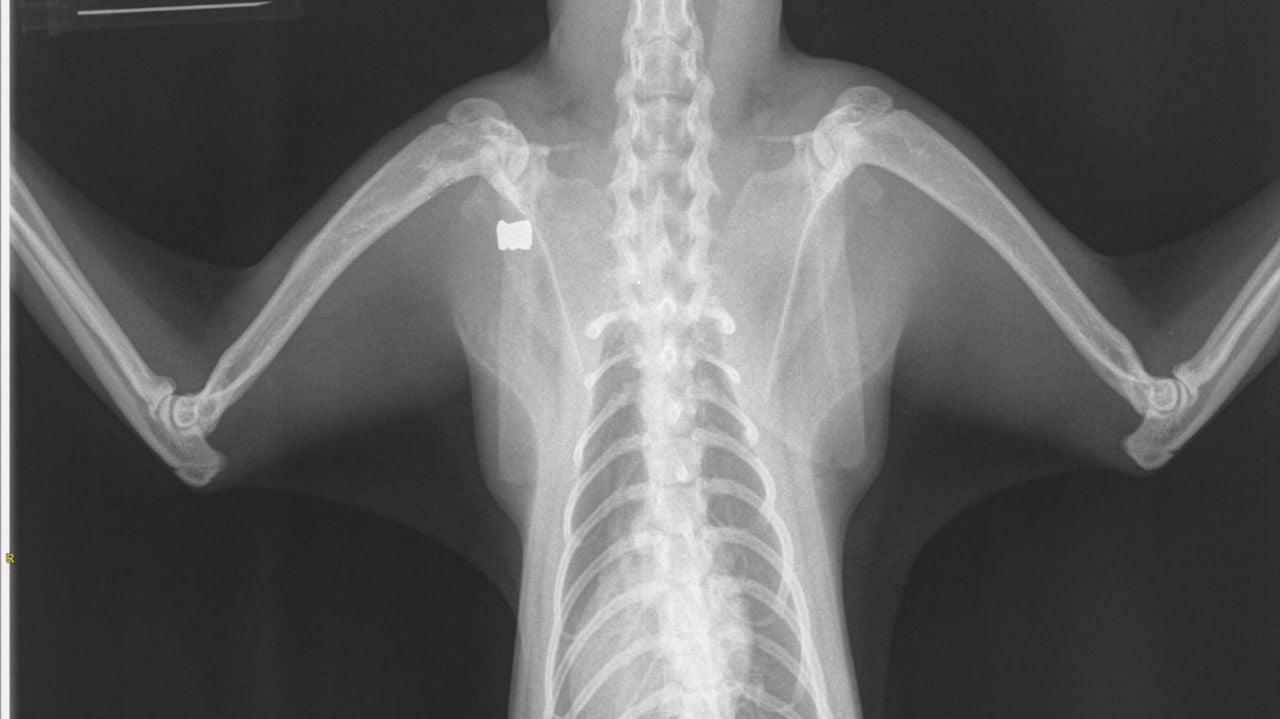

De kat overleefde de aanslag, maar het was volgens de dierenarts niet mogelijk om het kogeltje te verwijderen. De kat zal daarom altijd mank blijven lopen.